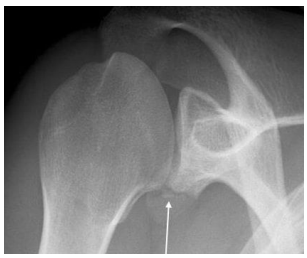

Um paciente de 18 anos de idade sofreu luxação traumática de ombro ao realizar saque durante jogo de tênis. Após redução da luxação em pronto-socorro, foi realizada a radiografia mostrada na imagem.

Com relação a esse caso clínico, é correto afirmar que, na radiografia, a seta aponta para uma lesão de